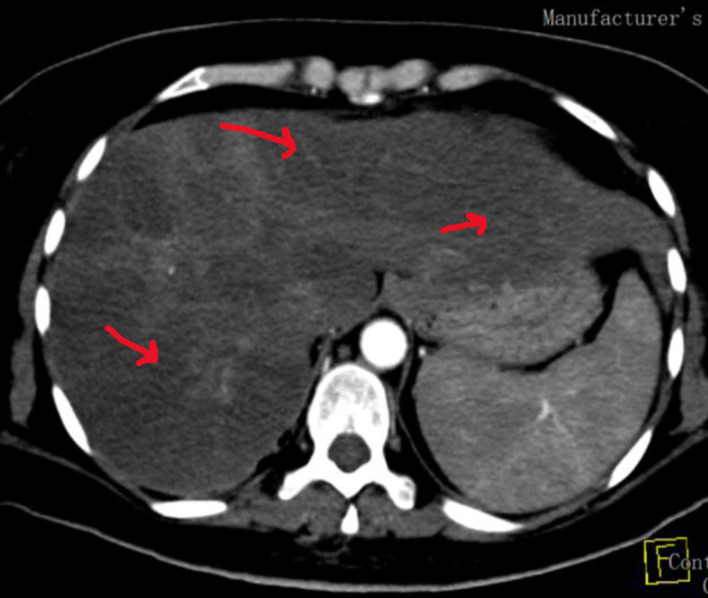

Catastrophic antiphospholipid syndrome (CAPS) is a rare, severe, and life-threatening form of antiphospholipid syndrome (APS). Early recognition and rapid treatment are of great importance to improve patient outcomes and decrease mortality. Herein, we present a case of lupus and APS with obstetric complications, recurrent thrombosis, and renal and hematological manifestations of APS which showed great response to the treatment.

Abstract Image